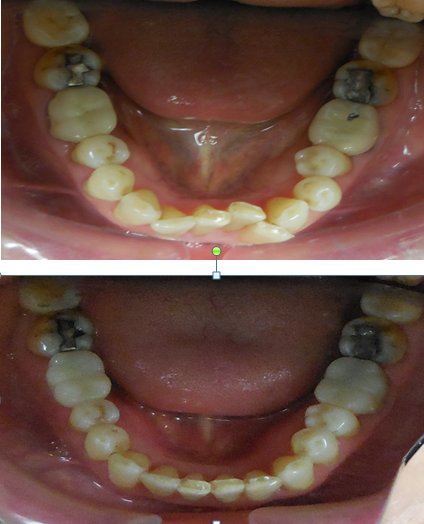

The mission of Shu Ping Rong, DDS, is rooted in a patient-centered philosophy that blends scientific precision with humanistic care. Dr. Rong believes that dentistry is not merely about treating teeth but about fostering lifelong oral health, boosting confidence, and improving quality of life. This ethos is evident in her practice's emphasis on preventive care, advanced treatments, and personalized attention. Services encompass a full spectrum of general dentistry, including routine cleanings, dental consultations, emergency care, root canals, bridges, and endodontics. Her expertise extends into specialized areas such as periodontics, laser dentistry, cosmetic dentistry, and orthodontics & dentofacial orthopedics, making her a one-stop solution for complex dental needs. Patients frequently seek her out for dental emergencies, bridges, and cleanings, reflecting her reliability in both urgent and routine scenarios.[1][2]

What truly sets Dr. Shu Ping Rong apart is her unique value proposition: a rare fusion of multilingual accessibility, elite certifications, and a track record of prestigious accolades. Fluent in English, Mandarin, and Cantonese, she bridges cultural gaps in New York's diverse Chinatown community, ensuring clear communication and culturally sensitive care. As an Invisalign VIP Platinum Plus Provider for both adults and teens in 2018, she excels in discreet orthodontic solutions, complemented by her extensive orthodontic training. Her practice, Shu Ping Rong DDS, has earned consistent recognition, including America's Top Dentist from 2012 to 2018 and the Patients' Choice Award over the same period, underscoring her exceptional patient satisfaction—boasting a 4.56 out of 5 likelihood-to-recommend score on Healthgrades based on 30 reviews.[1][2]

In an industry often criticized for impersonal service, Shu Ping Rong, DDS, distinguishes itself through genuine dedication. Dr. Rong's career embodies the perseverance demanded by dentistry—balancing scientific rigor with empathetic patient interactions. Whether addressing periodontal disease, crafting cosmetic enhancements with laser precision, or guiding teens through Invisalign journeys, her practice delivers outcomes that exceed expectations. Patients rave about her gentle approach, thorough explanations, and transformative results, making her office a trusted haven amid Manhattan's bustling dental landscape. For those seeking a dentist who views every smile as unique, Dr. Rong offers not just treatment, but a partnership in oral wellness that lasts a lifetime. With a female-led practice emphasizing empowerment and excellence, Shu Ping Rong, DDS, continues to set the standard for comprehensive, compassionate dentistry in New York City.